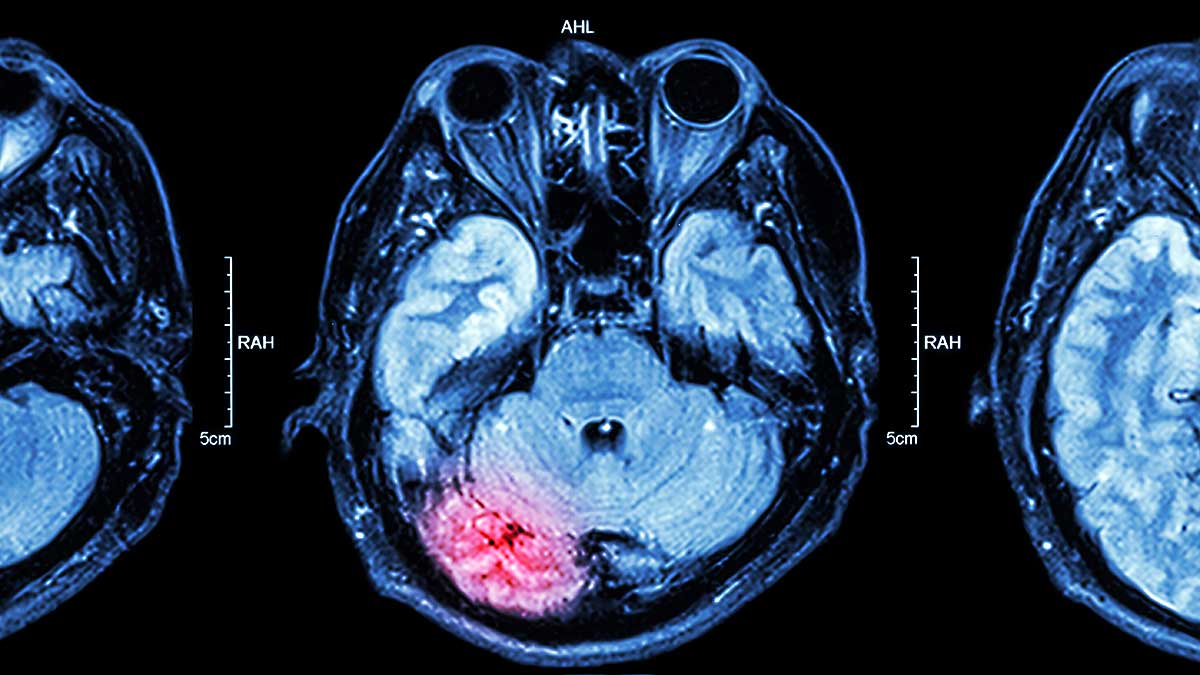

- Rezonans magnetyczny DTI (Diffusion Tensor Imaging)

- Ambulatoryjne EEG 48–72 godziny – wykrywa mikrodrgawki i zmiany fal mózgowych